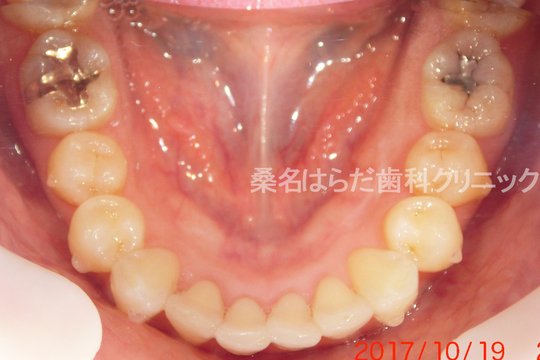

治療前

治療説明 歯科矯正でも目立ちにくい矯正方法であるマウスピース矯正で治療しました

治療期間 2年1か月

治療費用498000 円

治療後

治療の副作用(リスク)歯の動き方には個人差があり、予想された治療期間が延長する可能性があります。。マウスピースの使用状況、矯正歯科治療には患者さんの協力が必要であり、それらが治療結果や治療期間に影響します